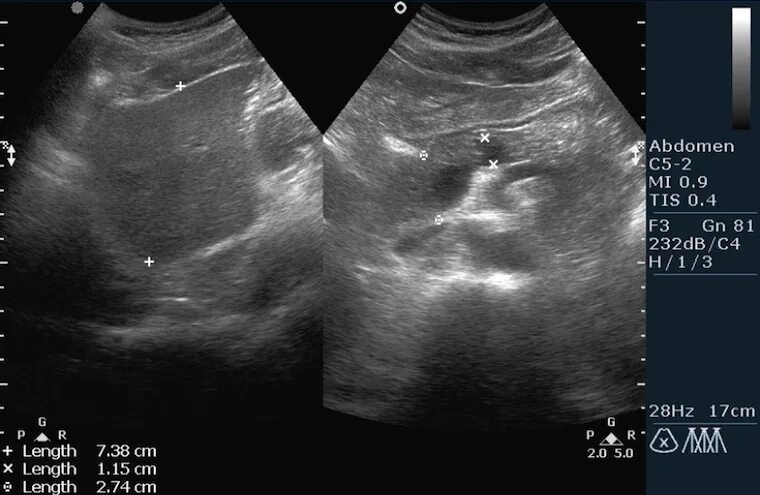

Симптомы диффузных изменений паренхимы поджелудочной железы